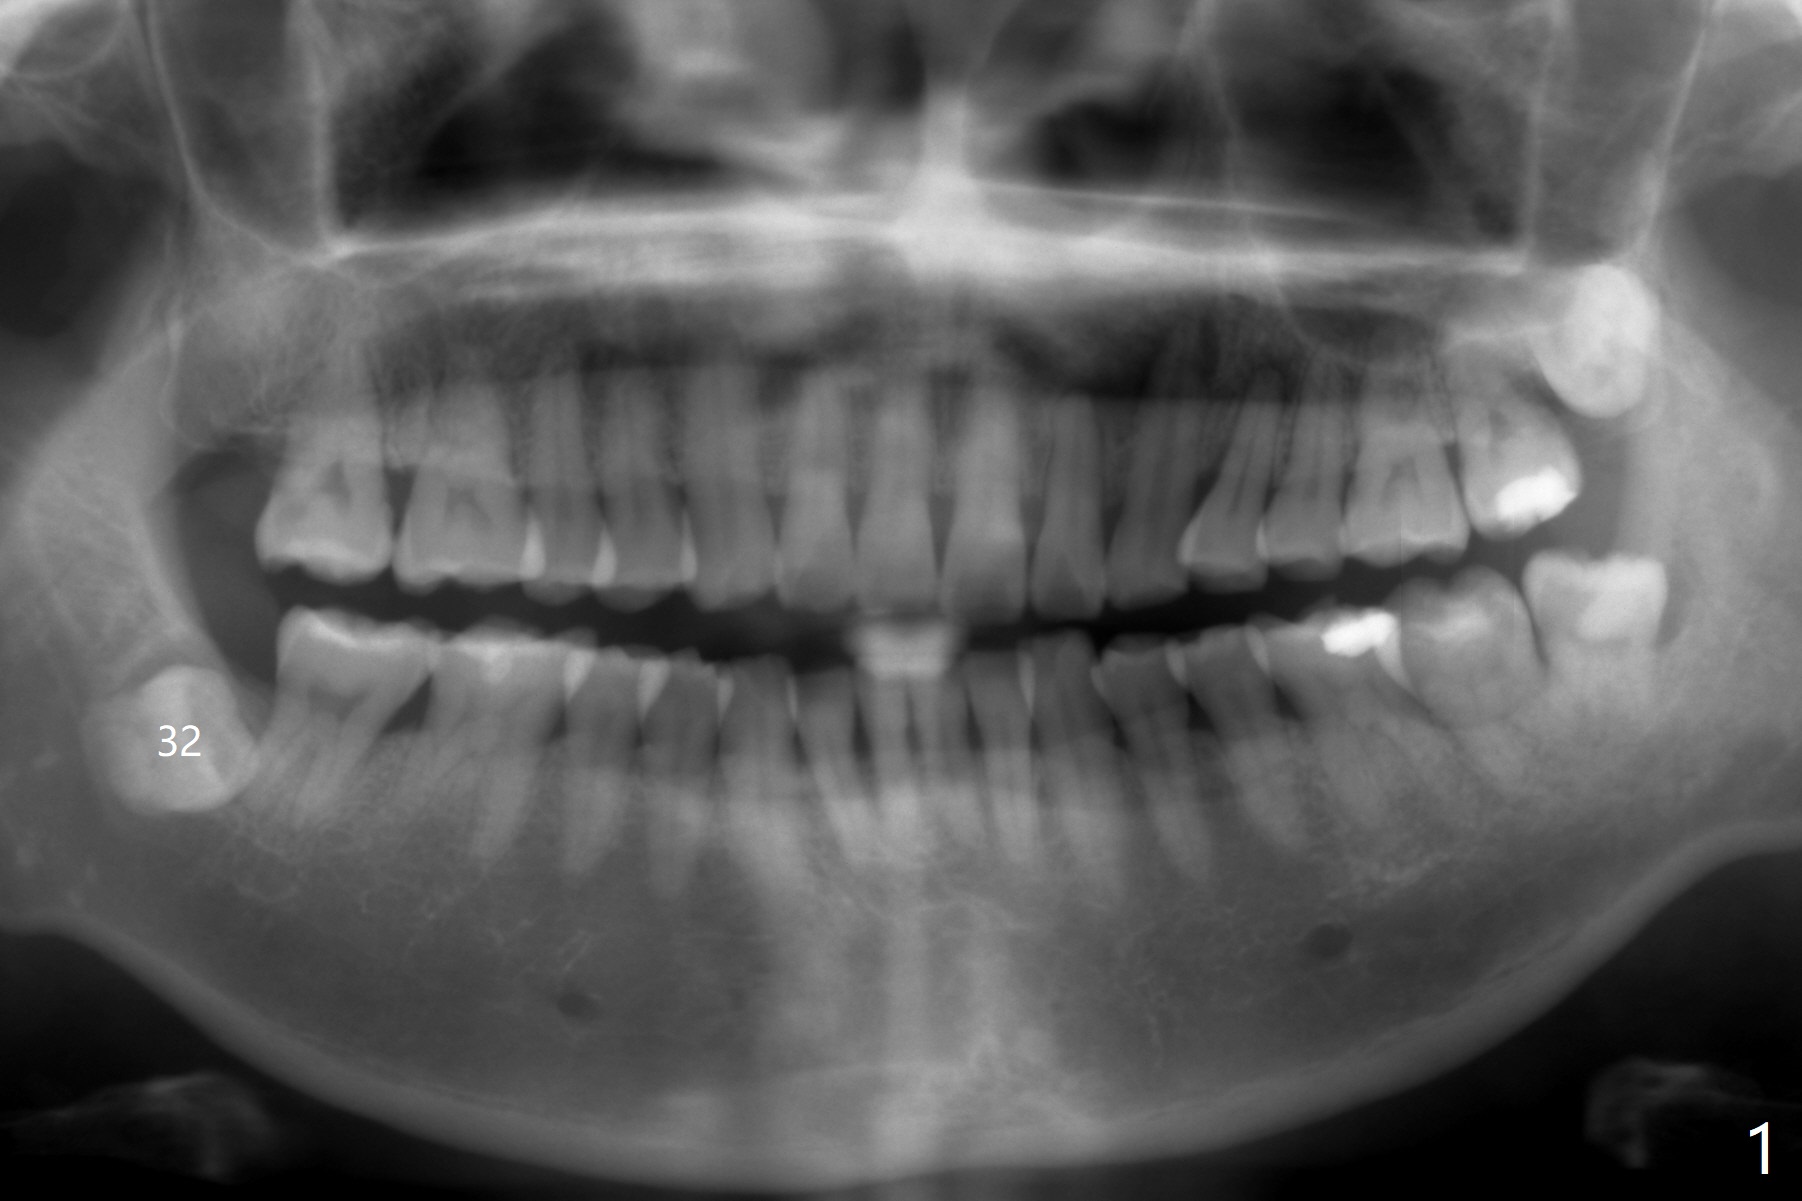

A 44-year-old woman agrees to have #32 extraction to alleviate #31 distal bone loss (Fig.1).  IANB, hockey-stick incision made, reflected mucoperiosteal flap, buccodistal trough, sectioned for multiple times, straight elevator/forceps removal, curette to remove tooth bud sac, copious irrigation, IA neurovascular bundle partially exposed, intact, + hemorrhage, packed with 1 piece of CollaForm plug and 1 and 1/2 Osteogen plug and Vanilla Cancellous/Cortical Mix in the socket, latter was washed out by bleeding, 4-0 plain gut suture, 2x2 gauze, hemostatic, watched in office for 1/2 hour, changed gauze once, hemostatic, bite block used during ext. Pt was doing fine, satisfied and with good anesthesia. Oral/written POI and extra gauze given. Amoxicillin, Medrol dose pak, Tylenol III, Called pt by the evening. She has mild pain in throat and mild swelling. Sensation returns. There is no hemorrhage.  Six days postop, "pain is being reduced".  There is light R facial swelling and localized induration.  No erythema is observed in the extraction site.  Six months postop, the tooth #31 has mobility I/II (Fig.2).  The patient can chew with it and is satisfied.  One year postop, "LR tooth loose. I dare not to use it". There is no BOP including #31 with mobility II.  There is bone regeneration at #32 socket 2 years 9 months postop (Fig.3).